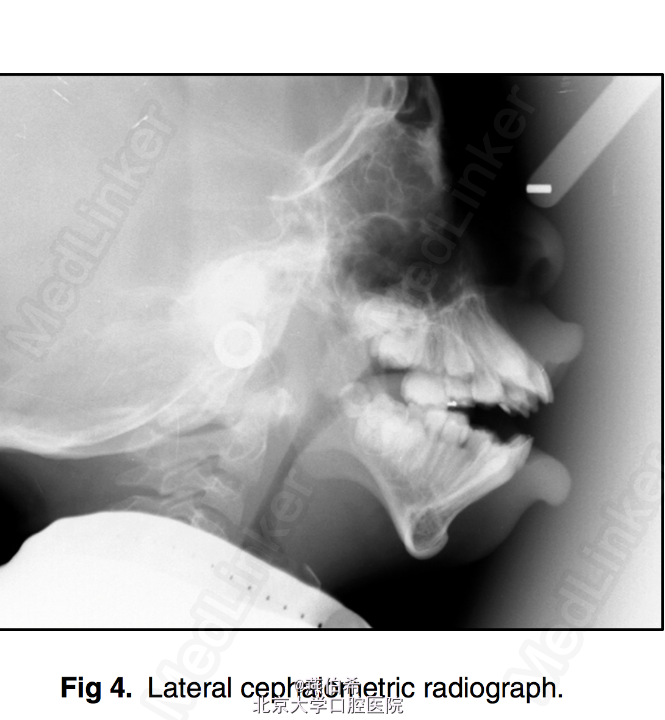

11岁非洲裔男孩,主诉牙不齐。 在New York-Presbyterian Morgan Stanley Children's Hospital (US news 儿科专业全美第9)接受颅面治疗,确诊为Treacher Collins综合征 婴儿时曾行气道造口,后右耳曾行鼓膜造口和置管以及左耳成型术

突面型,嘴唇无法闭合,口内10mm前牙开牙合,右侧3类磨牙关系,左侧1类磨牙关系。 头侧片显示极高角

Treacher Collins综合征 扩弓解决宽度不调,拔4个4矫正牙量骨量不调, 后行口外反L行截骨术矫正颌骨问题